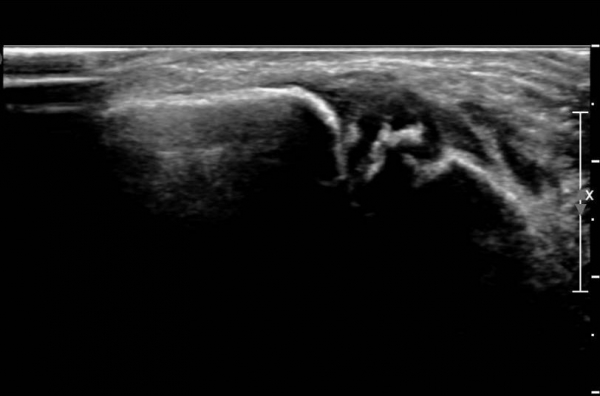

ÃÊÀ½ÆÄ ¼Ò°ß :  ¹ß¸ñ ¾Õ Á¾´Ü¸é°Ë»ç¿¡¼­ ¹ß¸ñ°üÀý³»  ¾à°£ÀÇ ¼ö¾×Àú·ù°¡ °üÂûµÊ(»çÁø 1).